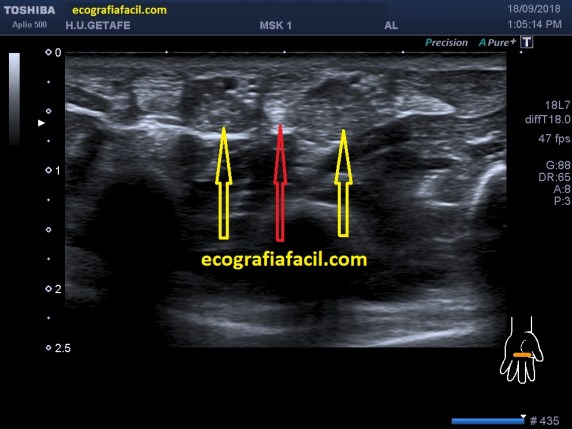

En el protocolo de exploración testicular te contaba cómo había que hacerlo y la semiología normal habitual.

Tenemos que tener claro que el testículo debe verse hiperecogénico y homogéneo y partiendo de esta premisa, realizar los cortes necesarios estudiando la anatomía testicular, incluyendo siempre, testes, epidídimo, cubierta y paquete vascular, es decir, dentro de la bolsa escrotal no nos dejamos nada sin ver.